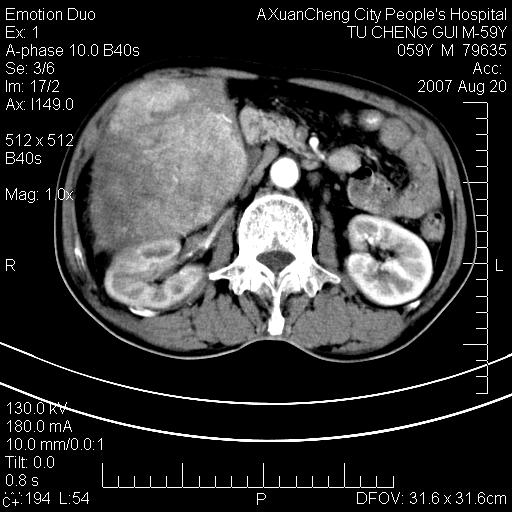

增强

典型的肝癌(巨块型)、腹水,有供血动脉。

典型的快进快出,动脉期可见肿瘤组织的供血动脉,肝下间隙可见条带状水样低密度区,符合原发性肝癌的ct表现。可以查一个afp >300有意义

动脉期肝右动脉粗细不均,走行有点迂曲,门脉期门脉右支有点受侵,并且中心有坏死,呈快进快出,符合肝癌

典型肝癌ct表现(肝右叶肿块密度不均,增强典型快进快出,内部有液化坏死,可能有脂肪变性)。